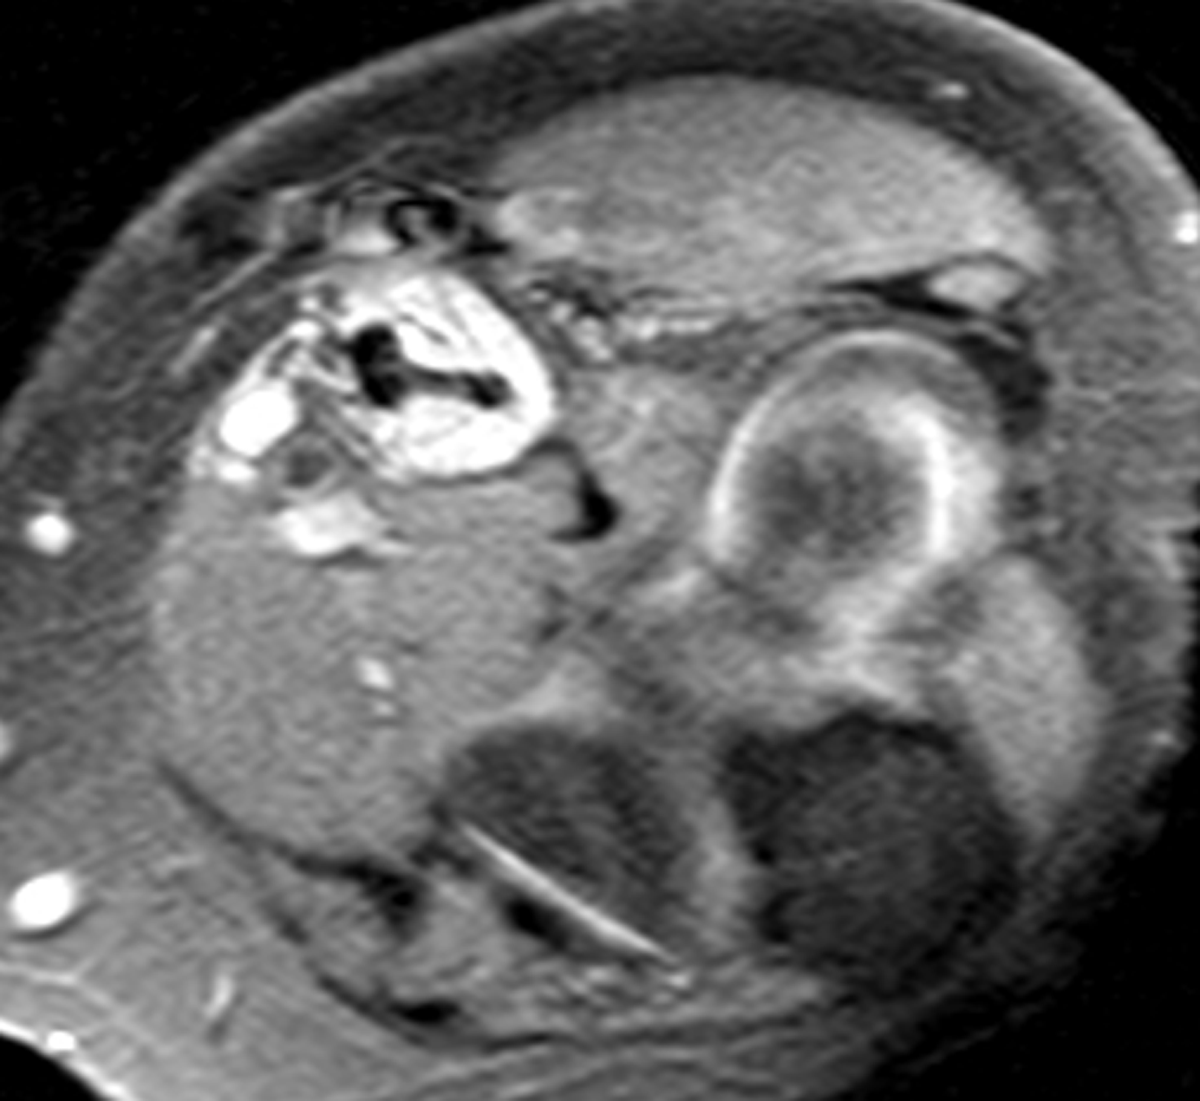

Figure 3

Fluid collection in the bicipitoradial bursa with high signal intensity on proton-density fat-saturated image, associated to injury to the distal biceps tendon.